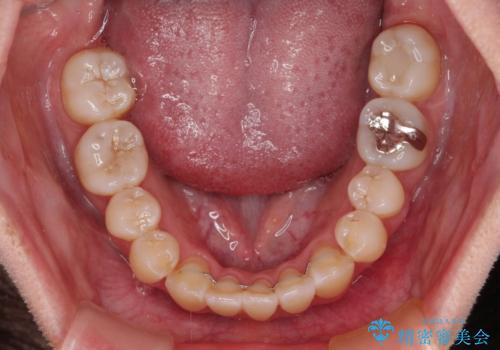

- 上下前歯の隙間と、外側を向いていて歯磨きのしにくい奥歯を気にして来院された患者様です。

下顎前歯が1本欠損しており、上下アーチはアンバランスとなりますが、インビザラインを用いて上下の隙間を改善しながら歯列を整えることとしました。

外側を向いている奥歯は、内側にアンカースクリューを埋入して牽引の固定ゲント氏、部分的にワイヤー装置を用いることで歯列に納めることとしました。